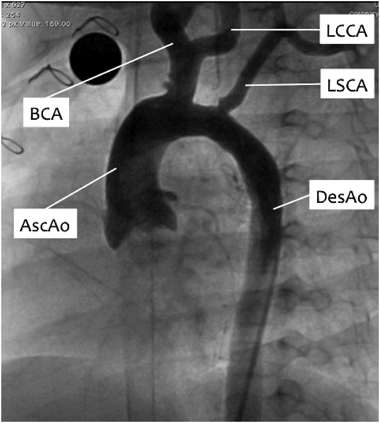

第5大動脈弓遺残に第4大動脈弓離断を合併した大動脈縮窄の2手術例Successful Repair of Coarctation of the Aorta Using Fifth Aortic Arch in Two Neonates with the Persistent Fifth Aortic Arch and Interrupted Fourth Aortic Arch